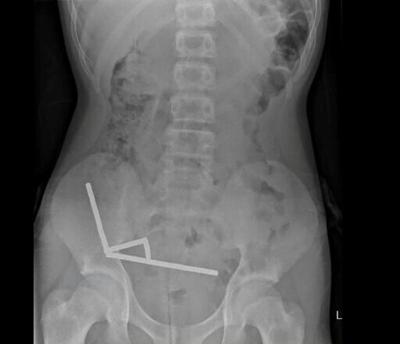

This undated handout released on October 24, 2025 from the New Zealand Medical Journal (NZMJ) shows an x-ray image of pieces of high-power magnets clumped up in the intestines of a New Zealand teenager in Tauranga

An X-ray showed the magnets had clumped together in four straight lines inside the child's intestines.

"These appeared to be in separate parts of bowel adhered together due to magnetic forces," they said.